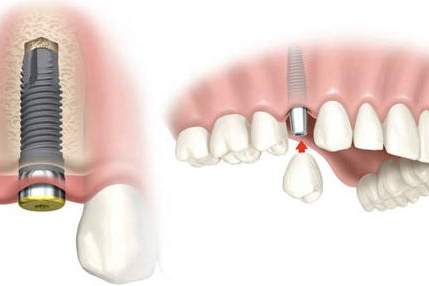

Los implantes dentales son elementos que se utilizan para sustituir a las raíces de nuestros dientes naturales, una vez integrados en el hueso alveolar pueden utilizarse para colocar sobre ellos prótesis fijas o removibles.

Los implantes dentales permiten que las personas sin dientes, puedan sonreír, hablar y masticar bien y confortablemente.